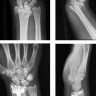

Upload Date: March 31, 2019 Full Size Image Dimensions: 272 × 474 Image Parent Post: Κατάγματα άνω άκρου

6.Εσωτερική οστεοσύνθεση κατάγματος κάτω πέρατος κερκίδας